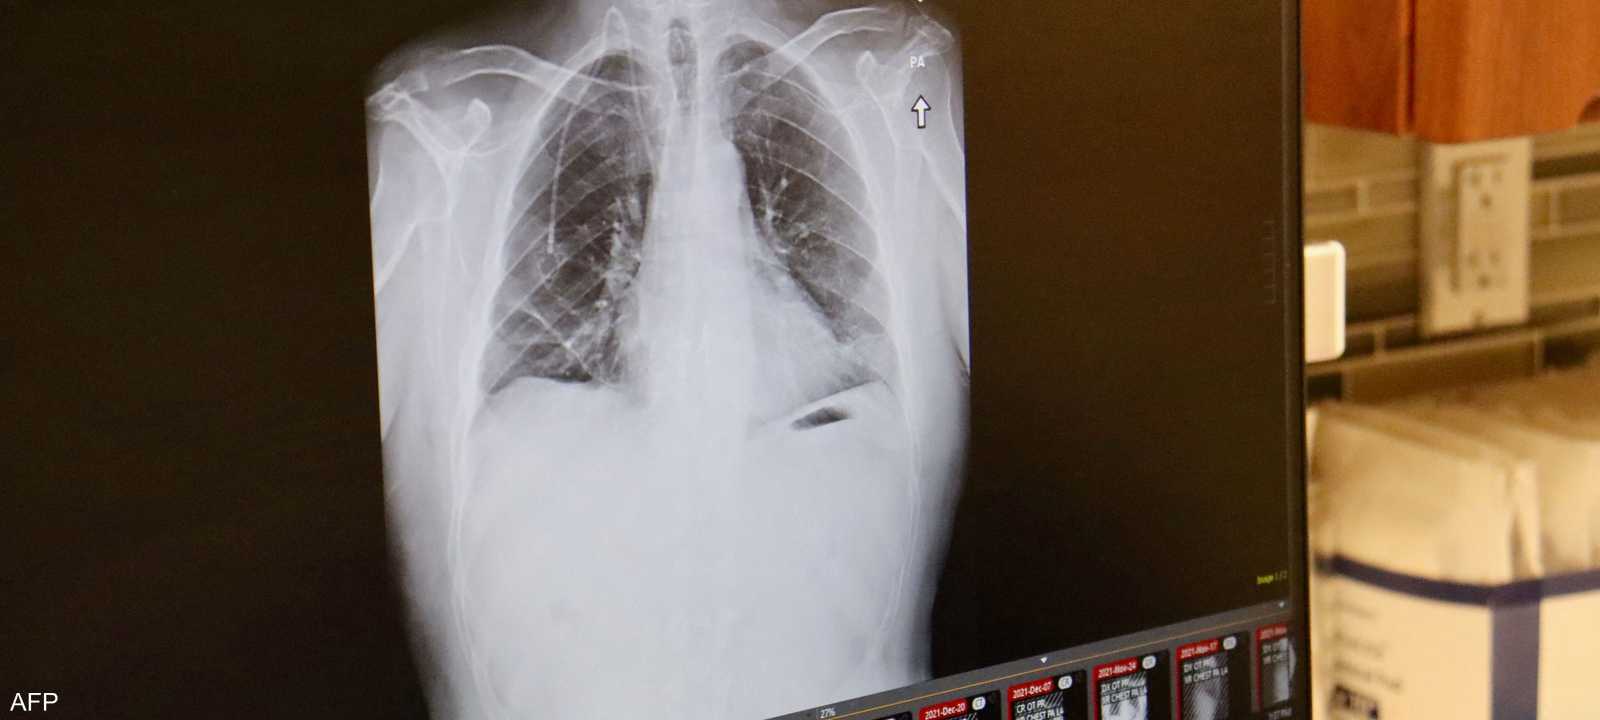

علماء يكشفون سر انتشار سرطان الرئة لدى غير المدخنين

ارتبطت الإصابة بسرطان الرئة منذ عقود بالتدخين، لكن زيادة نسبة الإصابة بهذا المرض لدى غير المدخنين دفع عدد من العلماء لتصنيفه كمرض مستقل يختلف عن فئات السرطان المعروفة سابقا، وله خصائص تميزه.